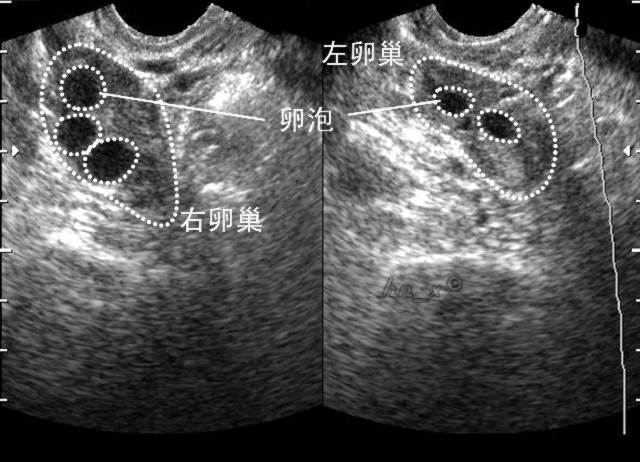

2. 超声监测排卵

超声监测是观察卵泡发育最直接、最可靠的方法之一。卵泡监测一般从月经的第3-5天开始。

月经3-5天:观察窦状卵泡数量(常用于月经失调的女性);

月经9-12天:常规开始监测卵泡,隔2-3天监测;

卵泡>15mm时:每天或隔天监测;

卵泡>18mm时:为成熟卵泡,此时可诱导排卵。

超声连续监测可见在排卵前卵泡不断长大,当最大的卵泡消失时,提示发生排卵。